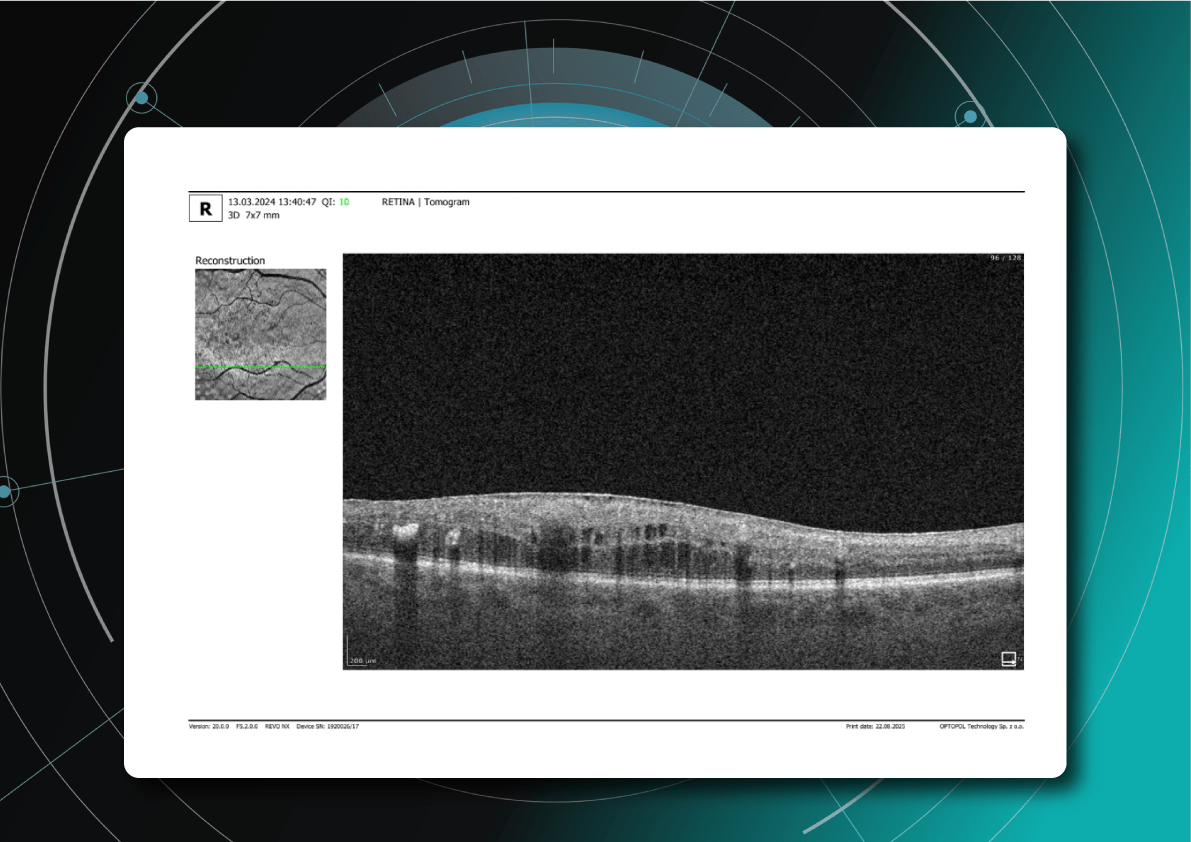

How does the standard report look?

OCT has become a golden standard for diagnosing and monitoring many ocular pathologies, thanks to its unparalleled level of detail in ophthalmic imaging.

While retinal reports vary among OCT models, they typically include:- a foveally centered B-scan,

- a quantitative thickness map,

- and a semi-quantitative thickness map.

The B-scan offers a visual snapshot of foveal architecture and confirms proper scan centering. The quantitative thickness map employs the ETDRS sector map to measure retinal thickness within a 6mm circle around the fovea, with specific measurements for the foveal sector (1mm), inner macular ring (3mm), and outer macular ring (6mm).

Progression analytics enable comparison of serial macular scans, which is invaluable for managing vitreomacular interface disorders and macular edema. The semi-quantitative thickness map provides a broader overview of retinal thickness throughout the scan.

Given this amount of data, it is challenging to identify subtle and localized retinal pathological changes. As a result, entire OCT datasets are represented by few aggregated values, and the standard OCT reports generated by most devices often rely on significant data reduction to simplify interpretation, which you can usually not customize.

Measuring treatment progress: biomarkers tracking, pathology progression

Imaging biomarkers are a particularly attractive option for clinical practice due to their non-invasive and real-time nature. Quantitative measurements of retinal thickness, fluid volume, and other biomarkers relevant to diseases like diabetic retinopathy and age-related macular degeneration aid in treatment monitoring.

OCT reports with customized measurements and selected biomarkers, retinal layers, or segments allow for precise focus on treatment monitoring and patient response to therapy. This personalized approach enhances clinical decision-making by highlighting each case’s most relevant information.